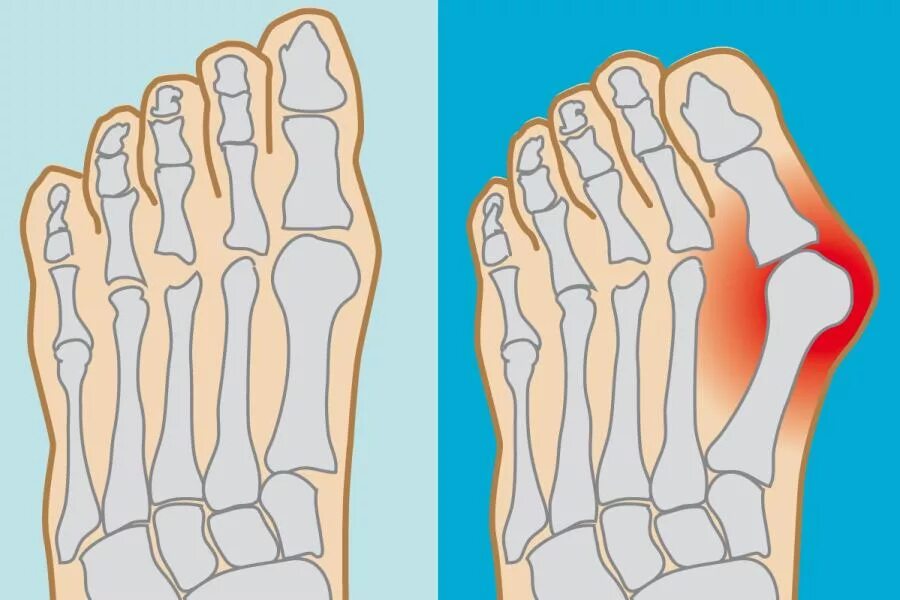

Операция деформации пальцев стопы